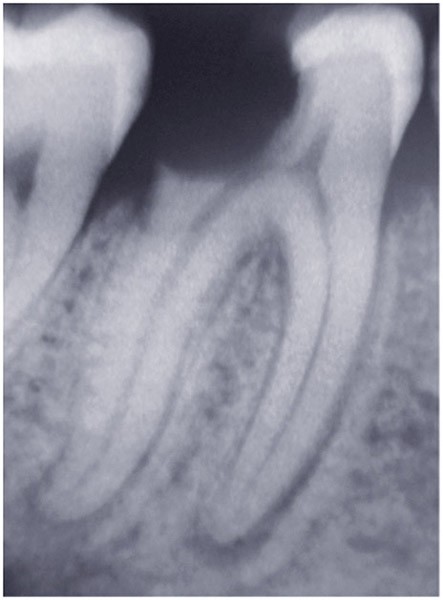

Dans un environnement parodontal sain, la chronologie des traitements conservateurs suite à la pathologie carieuse serait la suivante : le traitement endodontique de première intention, le retraitement endodontique et la chirurgie endodontique, voire l’amputation radiculaire. En cas d’échec, l’alternative implantaire pourra être envisagée (fig. 1).